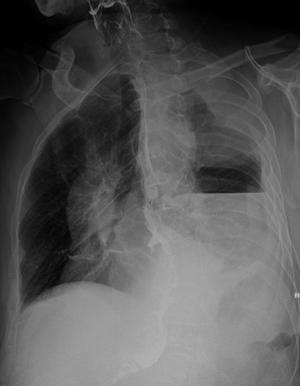

患者、男,66y,食道贲门ca术后13多天,不规则发热,来科照片:

考虑:1、食道胃胸腔吻合术后改变;

2、左侧液气胸;

3、图像欠清,右侧难以观察。

考不考虑左侧下肺背段脓肿?,那个气液平好像在肺内。

另外左侧肺尖区高密度影。是胸膜增厚吗?

1、胸腔胃,术后改变。液平面为胃泡影。

2、左侧胸膜增厚。

1、观察钡剂未流入气液平面内,考虑左后胸腔内包裹性气液平面改变

2、左侧胸壁包裹性胸腔积 液 结合临床病程行ct检查,

这是北京专家的会诊,(二炮总医院远程会诊结论)